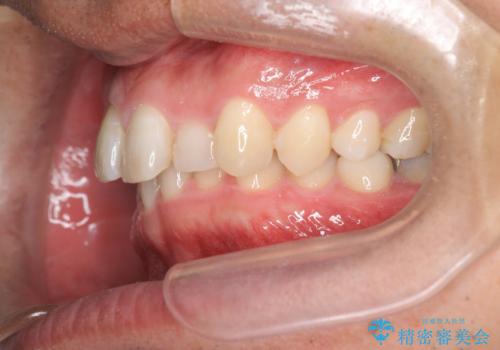

2級ディープバイト 遠心移動を伴うマウスピース矯正

・深い噛み合わせ(ディープバイト) ・2級性の咬合関係(上顎前突)・前歯のがたつき

深い噛み合わせと上顎前突の状態を治すのに時間がかかりましたが、治療後は理想的で安定した咬合関係となりました。